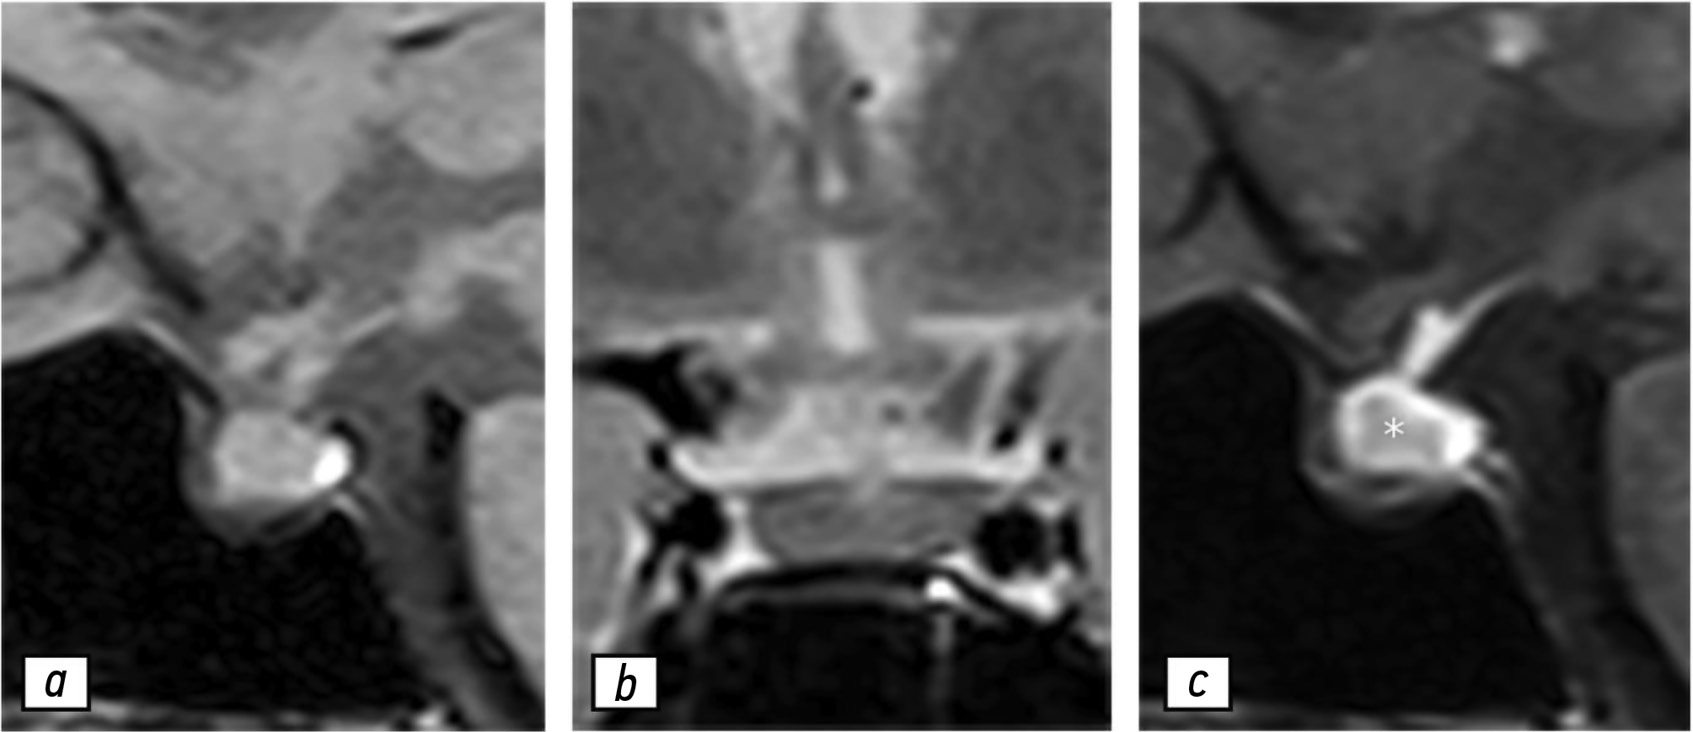

Результаты контрольной МРТ, выполненной в июле 2021 г., продемонстрировали увеличение гипофиза и усиление гетерогенности его структуры, что можно рассматривать как первые признаки гипофизита (рис. 2). В сентябре 2021 г. у пациентки не обнаружено каких-либо специфических симптомов, кроме головной боли. При проведении лабораторных исследований выявлено значимое снижение концентрации пролактина — 96,6 мМЕ/л.

Рис. 2. Результаты магнитно-резонансной томографии гипофиза, 09.07.2021: a — T1-взвешенное изображение в сагиттальной проекции; b — T2-взвешенное изображение в коронарной проекции; с — T1-взвешенное изображение в сагиттальной проекции с контрастированием. Отмечено умеренное увеличение гипофиза, усиление сигнала в его веществе (звёздочка) на T2-взвешенных изображениях (b), а также гетерогенное накопление контрастного вещества в центральной области гипофиза.